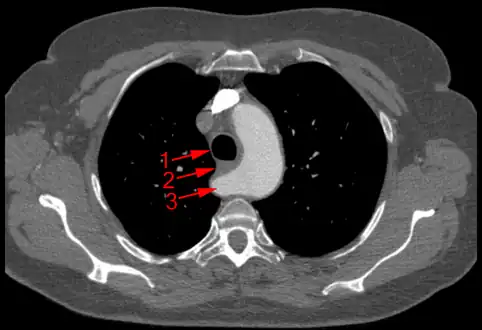

The evaluation of an aberrant subclavian artery can be done via CT angiography[7], which is a combo of CT scan with an injection of dye to produce images of blood vessels and/or tissues [8]